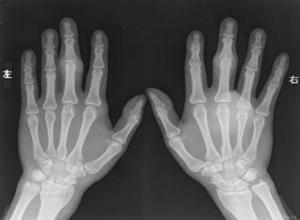

简介是第1跖趾关节的骨关节炎。极为常见,常由于第1跖骨位置变异引起,由于踝过度内转(旋前),趾向外偏(鉧外翻),第一跖骨背屈(高位跖骨),或第一跖骨长度增加或向内偏所致,偶尔外伤也是一个原因。